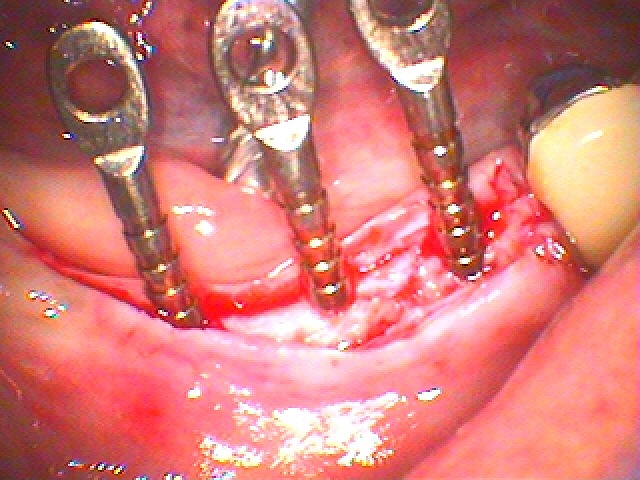

右下は3本欠損でした

骨幅も狭いです

このように埋入しています

骨密度もかなり高く出血の少ない硬い硬い骨でした

このように下顎管とも近いために埋入できないといわれたようです